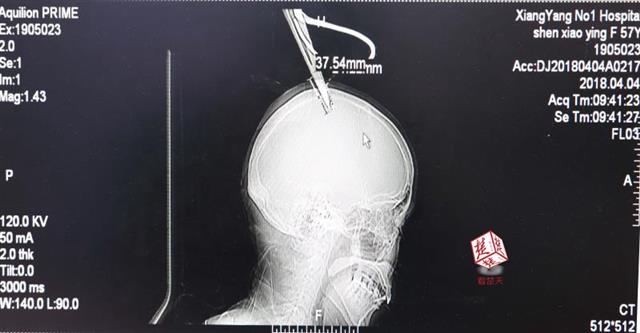

4月4日清晨,襄陽市樊城區(qū)太平店鎮(zhèn)57歲的農(nóng)村婦女沈某,在采摘香椿嫩芽時(shí),綁在竹桿上的剪刀因竹子腐朽不慎折斷,剪刀斜插入頭顱。經(jīng)過及時(shí)搶救,目前脫離生命危險(xiǎn)。

醫(yī)生檢查發(fā)現(xiàn),剪刀刀尖斜嵌在沈某顱骨里,離腦髓只有兩三毫米。所幸是斜著插進(jìn)去,如果是垂直刺入,很有可能造成癱瘓。

醫(yī)生檢查發(fā)現(xiàn),剪刀刀尖斜嵌在沈某顱骨里,離腦髓只有兩三毫米。所幸是斜著插進(jìn)去,如果是垂直刺入,很有可能造成癱瘓。最終經(jīng)過手術(shù),剪刀被取出,沈某目前仍在ICU進(jìn)一步觀察。